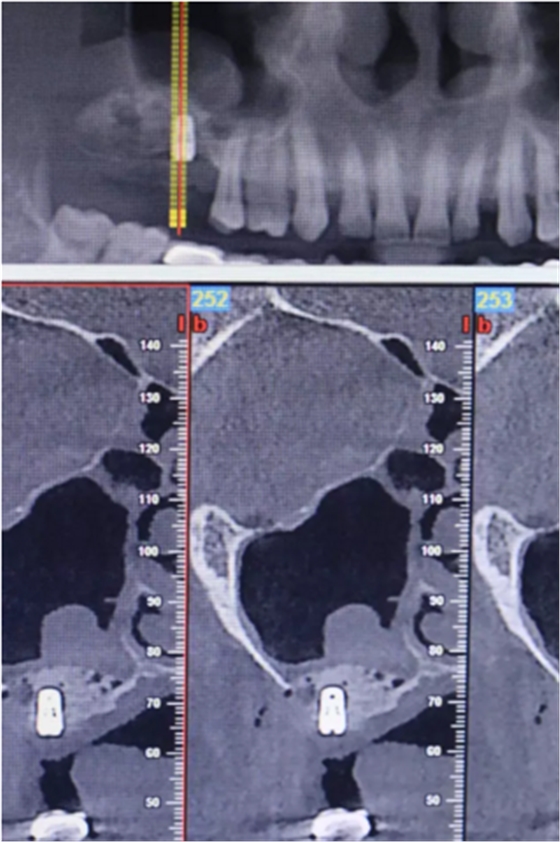

【病例分享】上頜竇大囊腫外提升